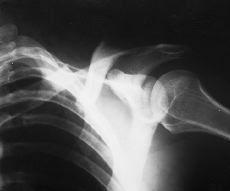

Paciente varón de 29 años de edad, sin antecedentes de interés, que sufre caída accidental con traumatismo directo sobre hombro izquierdo, presentando dolor e impotencia funcional en dicha articulación. A la exploración física se objetivó dolor y deformidad en hombro izquierdo con signo de la tecla positivo, sin déficit vasculonerviosos distales. En las radiografías realizadas (Fig. 1) se apreció una fractura de tercio medio de clavícula izquierda desplazada, asociada a luxación acromioclavicular tipo II de la clasificación de Tossy y cols.6,7 Fue intervenido quirúrgicamente, realizando reducción y fijación de la fractura de clavícula izquierda con placa DCP, así como revisión de los ligamentos acromioclaviculares, en los que se comprobó su integridad y fijación de la articulación acromioclavicular con dos agujas de Kirschner (Fig. 2). El paciente fue inmovilizado con sling, cursando el postoperatorio sin ningún incidente; las agujas se retiraron a las 4 semanas (Fig. 3) y tras un período de 3 años de seguimiento se observó una movilidad completa e indolora, alcanzando arcos articulares en el hombro afectado comparables al lado sano, así como unos resultados funcionales en los que se alcanzó una puntuación máxima en la escala de Constant2,25,20 (25/30) (Figs. 4 y 5).

Figura 3. Fractura una vez retirada las agujas a las 4 semanas.